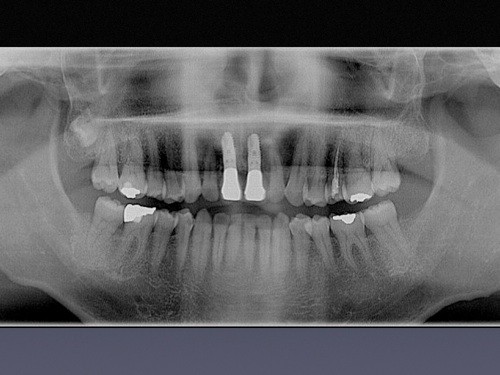

また、診断にはCTによる高解像度の3D撮影を活用しています。立体的な画像情報をもとに口腔内の状態を詳しく確認しながら、精密で安全性に配慮した治療計画を立てています。こうした設備を活用することで、より正確な診断と治療につなげています。

また、インプラント治療を安全に行うためにCT分析ソフト「SimPlant」を活用し、診断とシミュレーションを実施しています。

三次元シミュレーションにより、顎骨全体の状態や骨量、神経の位置を確認し、埋入位置や角度を事前に検討しています。

さらに、安全・安心・正確なインプラント治療を目指し、ガイド手術を行っています。

シミュレーションに基づいた計画を反映させることで、適切な位置への埋入につなげています。